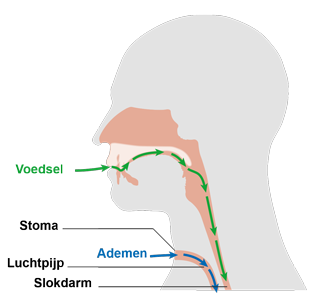

De patiënt zal ademen langs een opening in de hals.

Normaal wordt de ingeademde lucht eerst verwarmd, bevochtigd en gefilterd door de neus alvorens de ingeademde lucht in de luchtwegen komt.

De lucht komt nu rechtstreeks van buiten in de luchtwegen en de longen. Dit geef aanleiding tot prikkeling van het gevoelige slijmvlies van de luchtwegen en de longen. Het gevolg is dat de patiënt overvloedige fluimen ophoest langs de halsopening. Om hygiënische redenen dragen bijna alle patiënten een speciaal halsdoekje of een sjaal. Deze doekjes kunnen aangekocht worden bij de zelfhulpgroep.

De halsopening vraagt ook speciale zorgen.

De eerste dagen na de operatie en tot de halsopening goed genezen is, draagt de patiënt een canule om de halsopening goed te laten genezen. De halsopening (of stoma) vraagt speciale verzorging. Slijmen en korstvorming rond de halsopening moeten regelmatig verwijderd worden. Het afdekken van de stoma is noodzakelijk om hygiënische redenen.